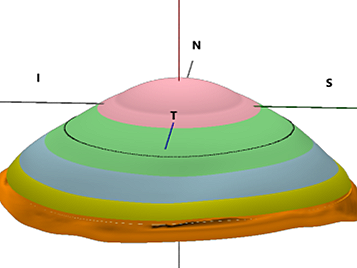

Custom Scleral Lenses

When customizations are needed or when conventionals fall short. Includes scan-based, freeform, and EyeFitPro (impression molding). 40,000 data points are collected to create a custom fit lens.

Ultra Custom Scleral Lenses

For the ultimate precise fit and full customization options utilizing impression molding (EyePrintPro). 80,000 points of data are collected to create a truly unique scleral lens.

Scleral Lenses: Customization Options

Bi-elevation™ to reduce or eliminate midday fogging